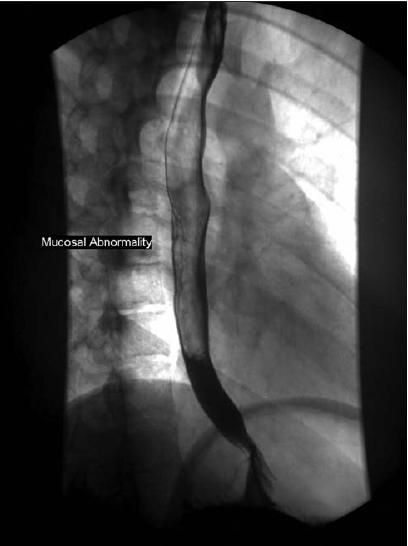

Fluids and lansoprazole were started intravenously.The patient's esophagram and upper endoscopy findings are shown

The esophagram in the second patient showed evidence of mucosal thickening in the lower one-third of the esophagus, suggestive of some edema in the mucosa secondary to esophagitis. The findings of barium esophagography in both patients were consistent with the findings of the upper endoscopy.